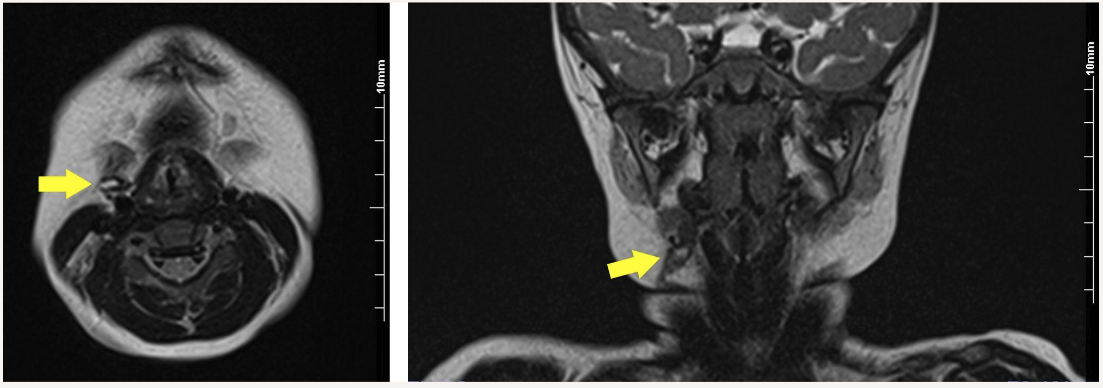

Magnetic resonance imaging (MRI) showed that the tract was located between the right submandibular gland and common carotid artery to the subcutaneous tissue. High signal intensity, considered a liquid component, was observed inside the tract on a T2-weighted image (Figure 2).